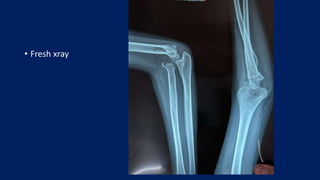

• Fresh xray